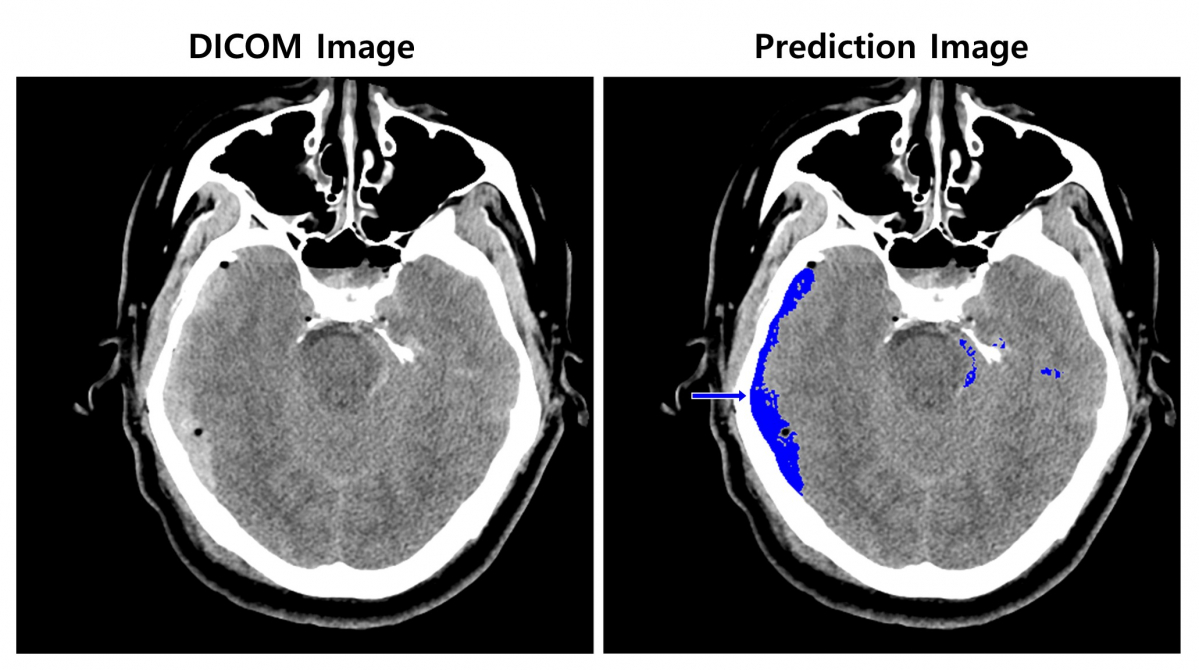

▲뇌출혈 영상 판독 AI 모델 이미지. (사진제공=SK(주) C&C )

SK㈜ C&C는 1차 아주대학교의료원에 이어 2차로 서울대학교병원의 CT 영상을 활용해 ‘뇌출혈 영상 판독 AI모델’을 개발했다. 이 모델 학습에는 SK㈜ C&C 비전 AI(Vision AI)의 이미지 세그멘테이션 기술과 총 8만여 장의 뇌 CT 영상 및 판독데이터를 활용했다.